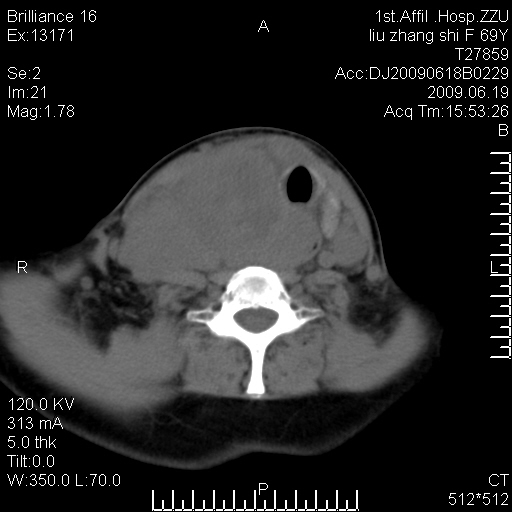

标题: CT26782:女,69岁,颈部占位,3天后公布病理结果。

【病理证实系列】女,69岁,颈部占位,有病理结果,3天后公布。(由于病例时间较久,临床资料不全,请网友见谅)本系列将有几百种常见、少见及罕见病例,均经病理证实。病例资料来自郑州大学第一附属医院。与网友共享,本人有空就发。

甲状腺癌并颈部淋巴结转移。感谢楼主的良苦用心,谢谢。

甲状腺癌并颈部淋巴结转移。

需与鼻咽癌鉴别!

支持甲状腺癌广泛侵及周围结构并颈部淋巴结转移。

鉴别:淋巴瘤、恶性神经源性病变、恶性纤维组织细胞瘤。

病理结果:颈部非霍奇金淋巴瘤。

右侧甲状腺确实有问题